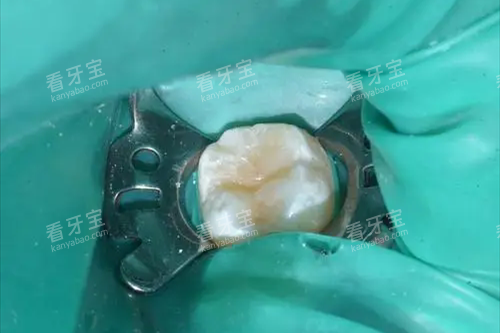

诊疗操作费

即医生的技术劳务费用,包括去腐、备洞、隔湿、填充、塑形、抛光等一系列精细操作。这部分费用在医院有明确的定价,私立医院则通常打包在总价中。

?显微治疗费:部分高端诊所会使用牙科显微镜进行操作,精度极高,费用也会上浮。